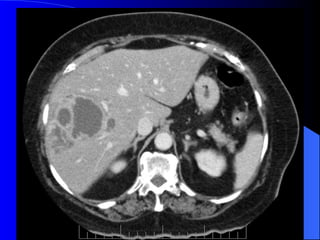

Absceso hepático piógeno DX por imágenes. Ecografia y TAC. Clínica Generalmente secundario.

Absceso Hepático